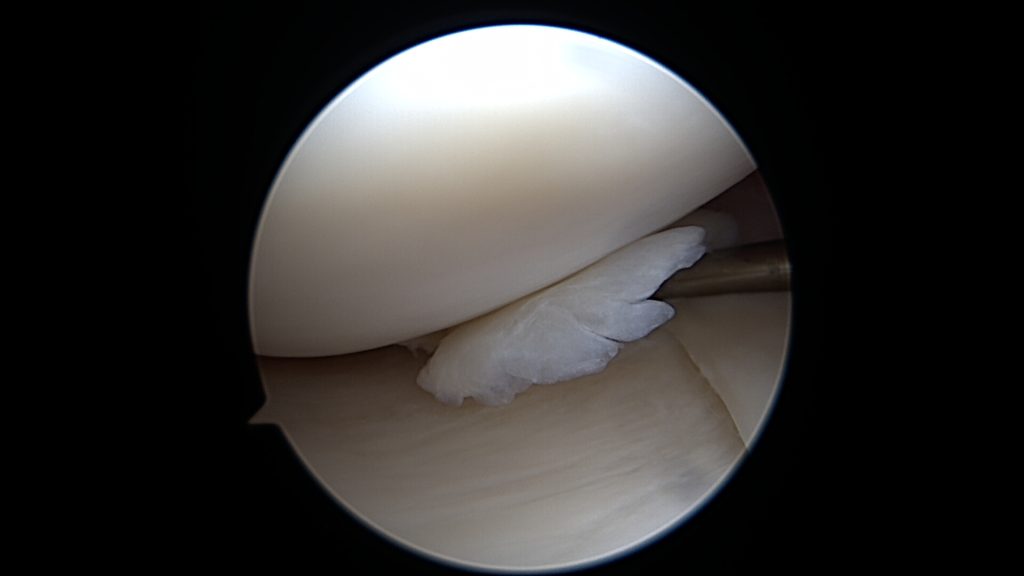

Jeśli jednak w trakcie urazu ulegnie ona większemu uszkodzeniu, rozkawałkowaniu, lub gdy będziemy zwlekać z zabiegiem operacyjnym, to po wprowadzeniu optyki do stawu naszym oczom ukaże się łąkotka rozwłókniona, popękana, w kilku kawałkach.

W tym przypadku jej proste przyszycie nie będzie możliwe, nie będzie po prostu stabilnych fragmentów łąkotki które można złapać szwem. Konieczne jest zastosowanie techniki „biokanapki”. Zabieg polega na owinięciu błoną kolagenową uszkodzonego fragmentu łąkotki, błona pełni tu rolę worka trzymającego włókna łąkotki razem. Szwy zakłada się poprzez błonę kolagenową stabilizując tym samym luźne uszkodzone fragmenty łąkotki. Na koniec zabiegu podaje się komórki macierzyste do środka stworzonej w ten sposób przestrzeni. Postępowanie pozabiegowe jest w tym przypadku określone odpowiednim protokołem rehabilitacyjnym.